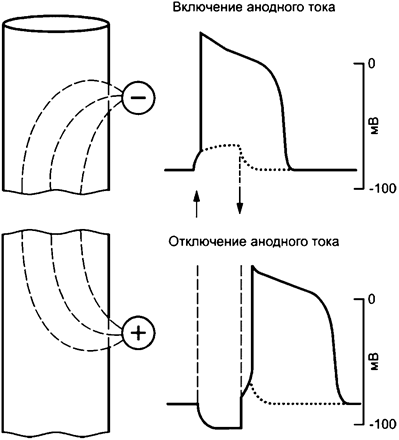

Эта реакция свойственна различным, не только нервным, видам клеток. Для клеток сердца она также характерна. Полярность тока влияет на реакцию чувствительности так же, как и на ФЖ (см. рисунок А.24).

Имеют место два вида возбуждения импульсами постоянного тока вследствие изменения мембранного потенциала клетки при включении катодного тока и отключении анодного тока. Потенциал действия возникает при достижении потенциалом мембраны соответствующего порогового значения.

Рисунок А.24 - Воздействие импульсами постоянного тока на одиночную клетку сердца